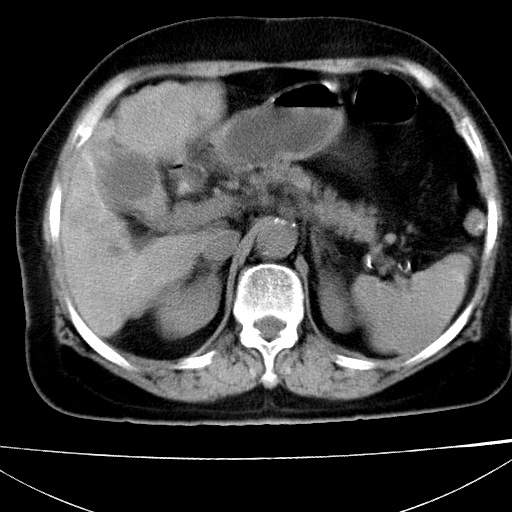

病人以胆囊癌手术的,病理结果为中分化腺癌。

现在看看肝右叶内圆形低密度影你们考虑什么呢?

肝内圆形低密度影考虑扩张的胆管

请看3mm重建像如下: